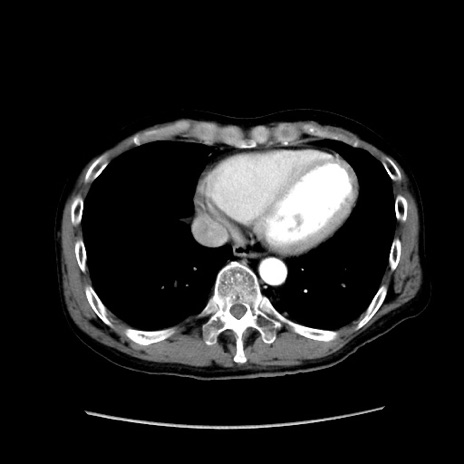

症例37(横断像)

【症例】40歳代 男性

【主訴】腹痛

【現病歴】4時間ほど前に電車に乗車中に臍部上より腹痛出現。徐々に増悪し起立困難となり、救急外来受診。生ものは数日食べていない。今朝お雑煮を食べた。

【身体所見】BT 36.8℃、BP 117/84mmHg、HR 91/min、SpO2 97%、苦悶様、腹部:臍上部広範囲圧痛あり、反跳痛±

【データ】WBC 8100、CRP 0.03